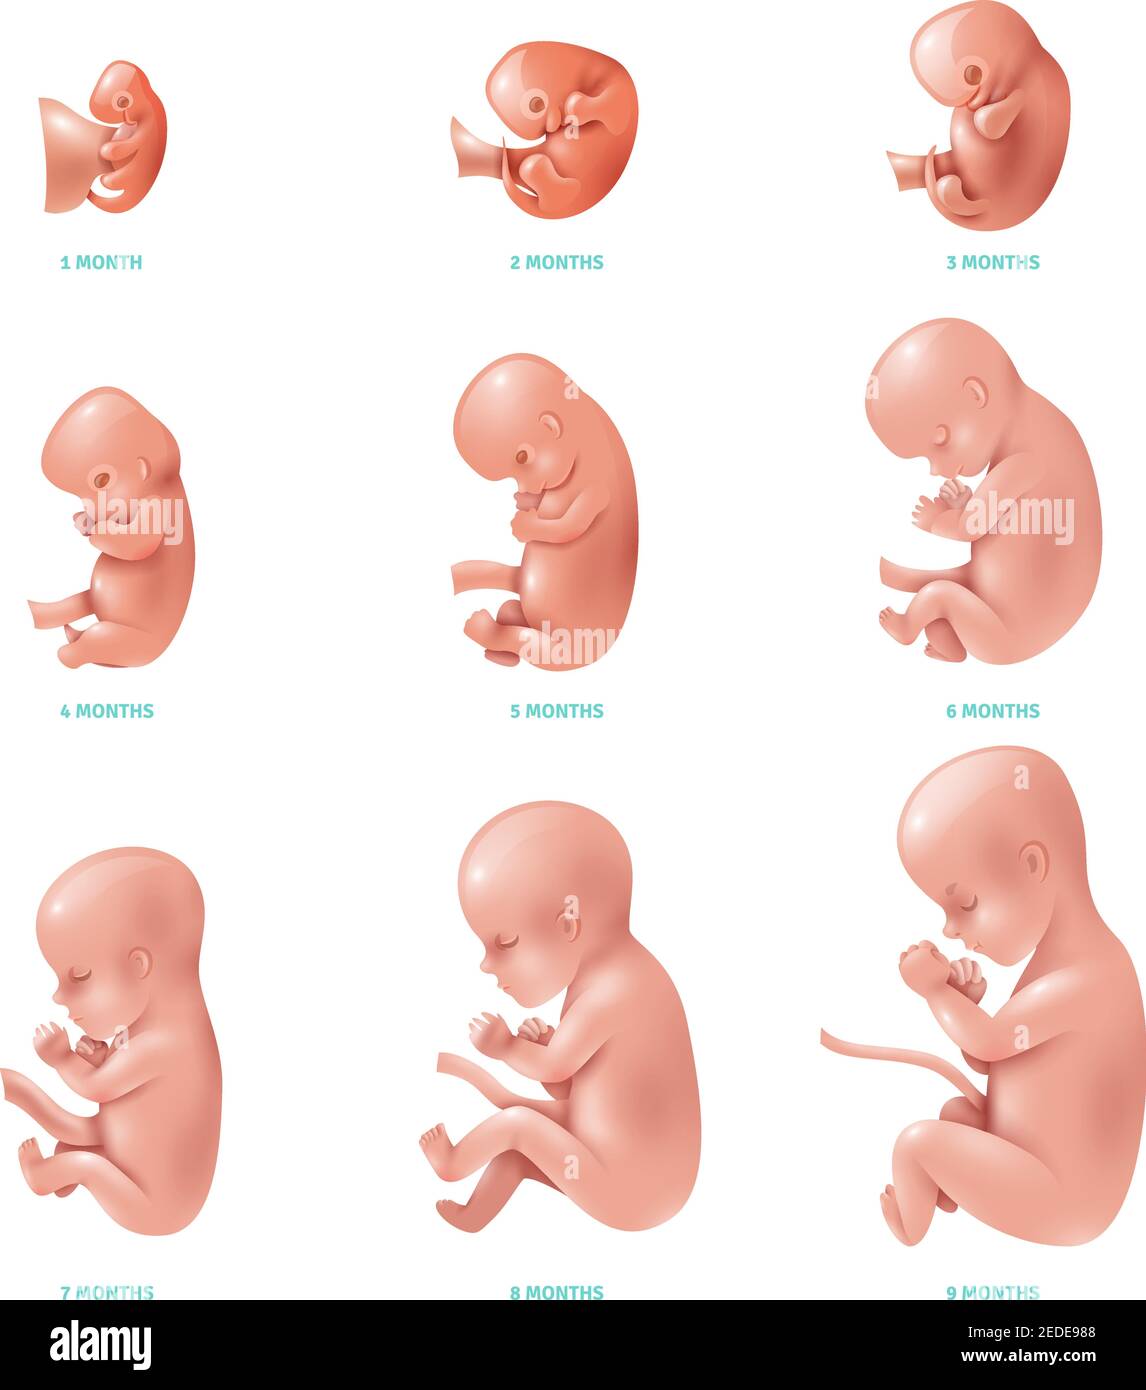

what does a 2 month old fetus look like

Posts: what does a 2 month old fetus look like